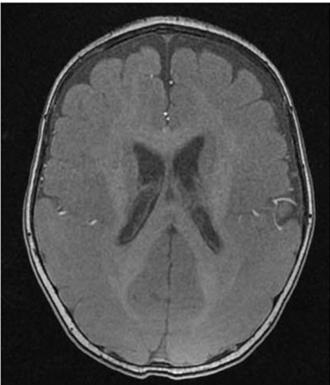

大腦沒皺褶!長庚、陽明交大找出「平腦症」致病基因

一般人類的大腦表面會有許多稱為「腦迴」皺褶,與高階認知功能發展息息相關,但有少數患有「平腦症」的人則沒有皺褶,恐嚴重影響幼兒發育,全台約有300例病例,高雄長庚陽明交大研究合作,繼2020年之後,再次發現造成平腦症的基因NDEL1,登上今年1月神經科學重量級期刊「神經病理期刊(Acta Neuropathologica)」,有機會讓人類進一步對大腦有深入了解。